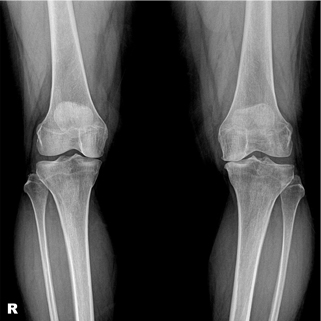

관절염의 수술적 치료로 인공관절 수술이 가장 흔하나, 인공관절수술은 일을 하고 운동을 해야하는 젊은 사람들에게는 시행하기 어려운 단점이 있습니다. 그래서 근위경골 절골술은 체중부하를 관절염이 생기지 않는 쪽으로 옮겨주는 방법입니다.

경골 교정 절골술 전

경골 교정 절골술 후